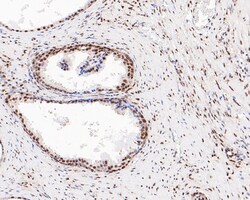

| Immunohistochemistry (Paraffin), Western Blot, Immunocytochemistry | |